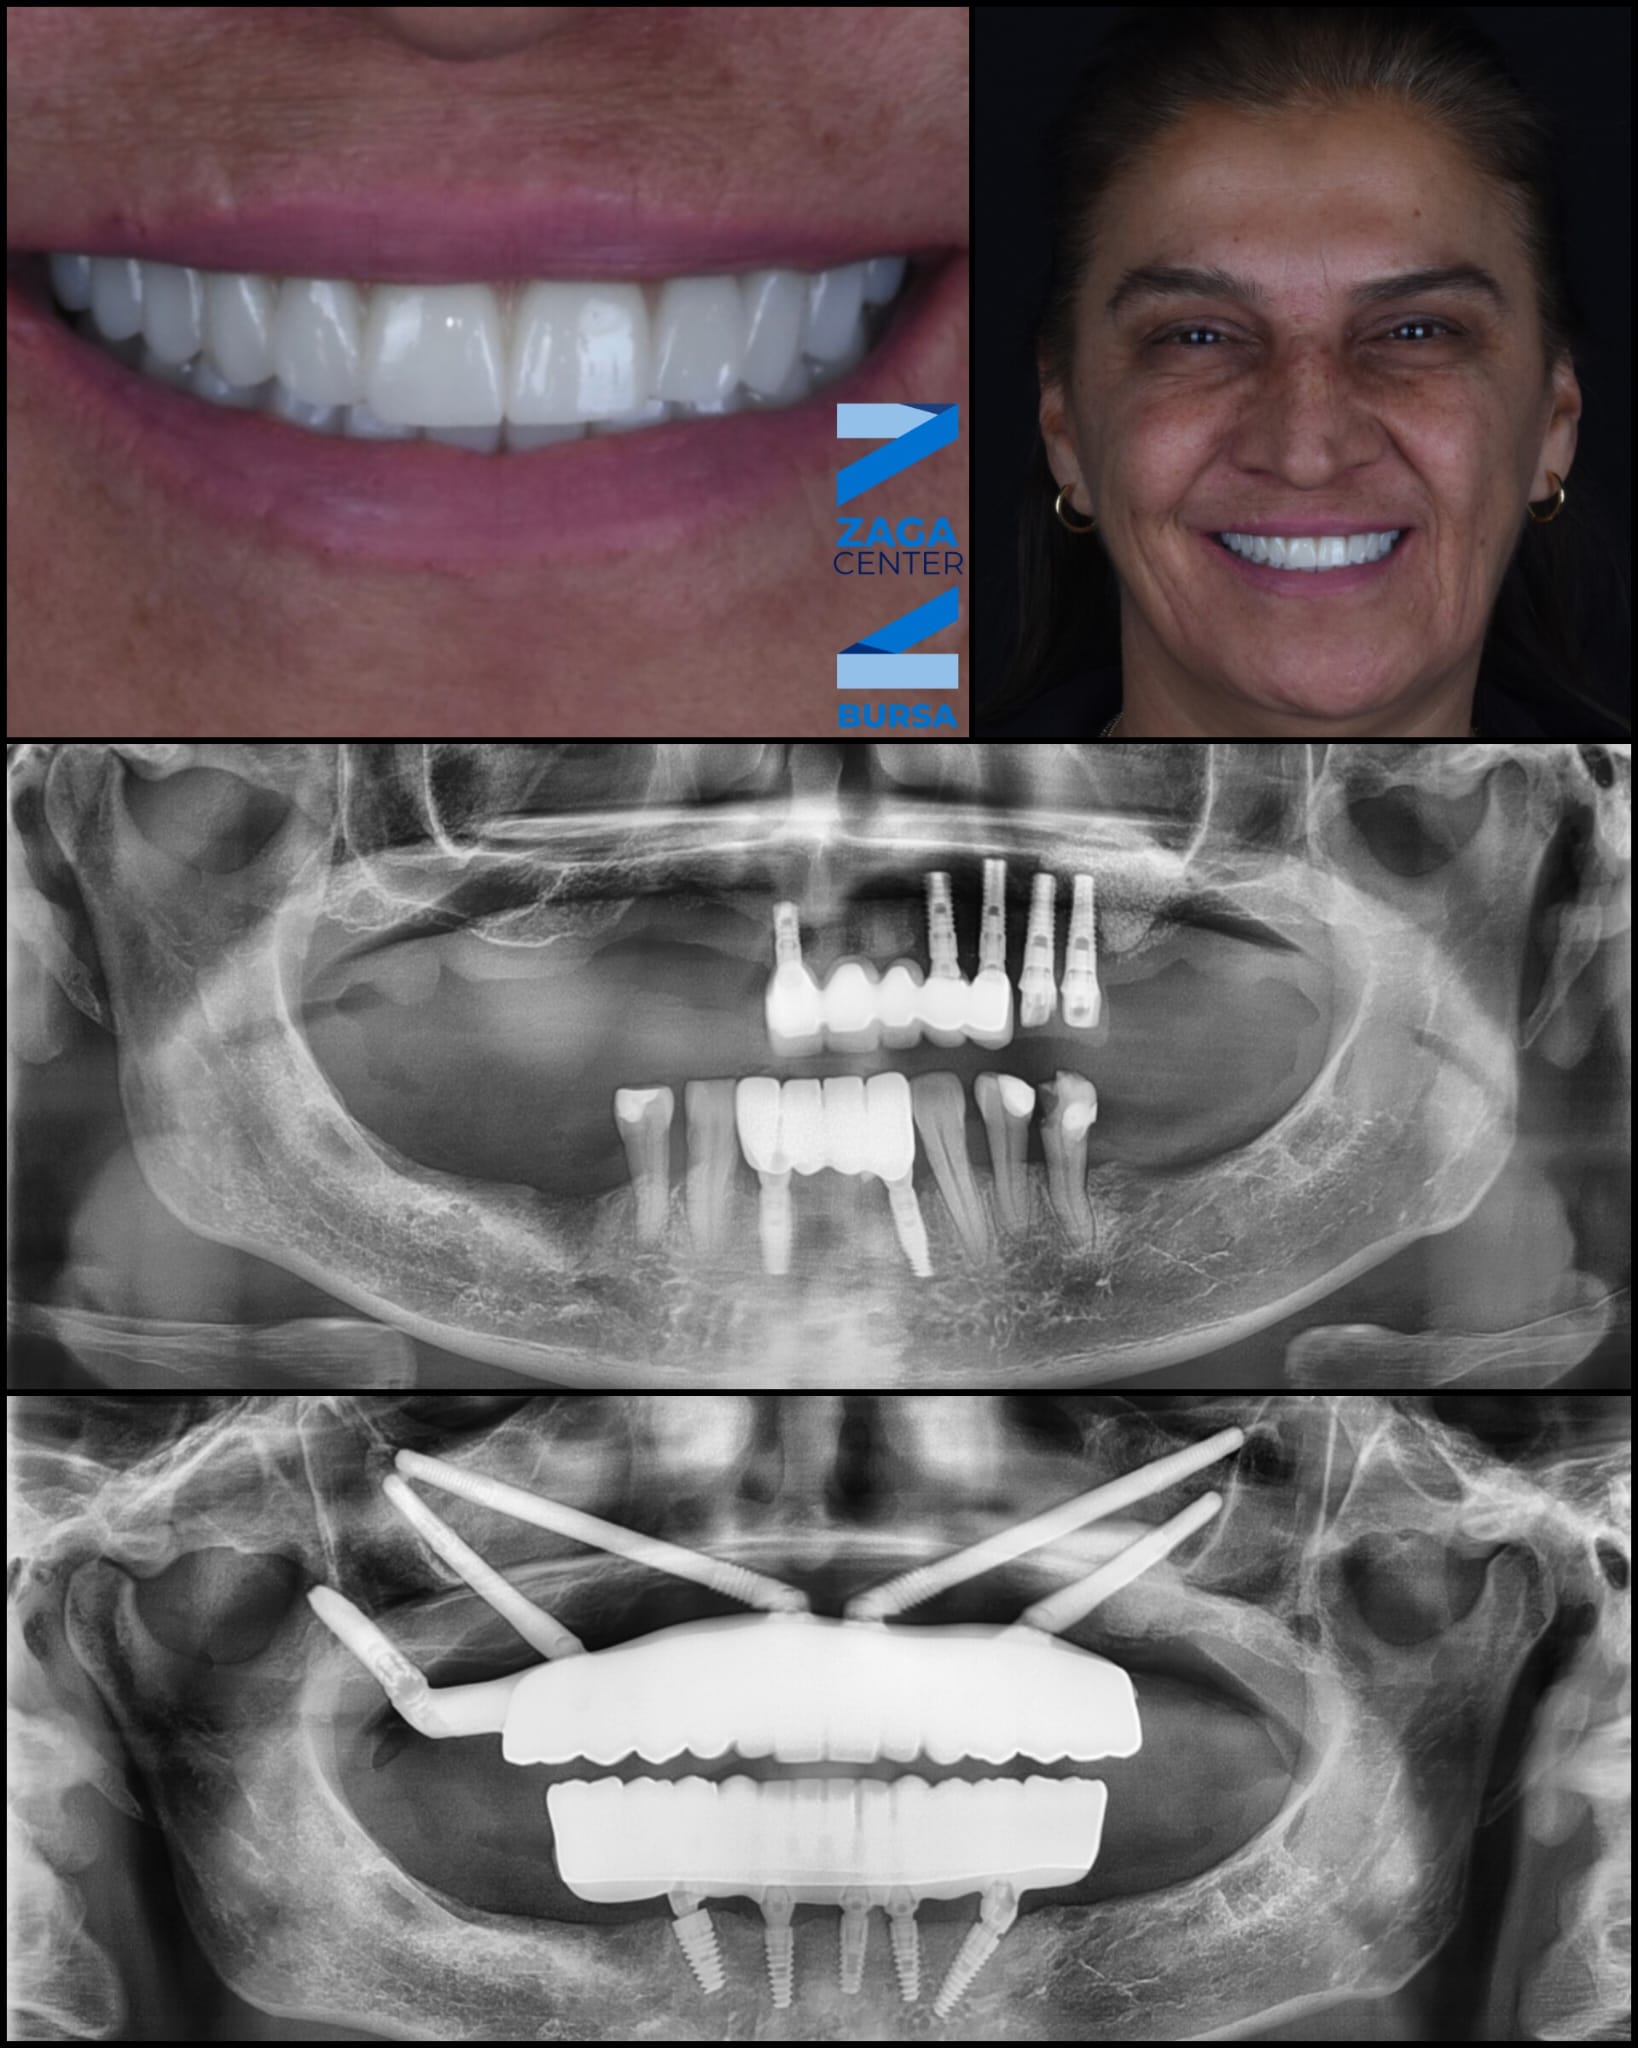

Zygomatic Implants Case Study

Case Study

Advanced Zygomatic

Implant Rehabilitation

Fixed prosthetic rehabilitation with zygomatic implants for a patient presenting with extreme bone deficiency and failed previous implant attempts from another facility.

In this complex case where traditional implant treatments were technically impossible to apply, the ZAGA Concept allowed us to provide a stable, long-term solution through specialized zygomatic surgery, restoring both function and aesthetics.

• Removal of failed implants from external centers

• Severe bone loss management via Zygomatic Concept

• Full functional and aesthetic fixed restoration